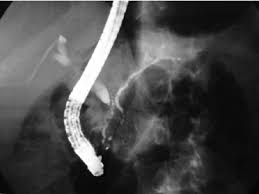

Chronic cholangitis is often treated with antibiotics to manage infections and procedures like endoscopic retrograde cholangiopancreatography (ERCP) or surgical interventions to remove blockages or place stents to restore bile flow.

Surgical repair or procedures such as ERCP or stent placement are commonly used to manage bile duct injury and restore bile flow.

The treatment for gallstones causing bile duct stricture often involves removing the gallstones through surgery or using ERCP to remove the stones and place stents to allow bile flow.

Treatment for choledochal cysts typically involves surgical removal of the cyst and repair of the affected bile ducts. If a stricture has already developed, procedures such as ERCP or surgery may be necessary.